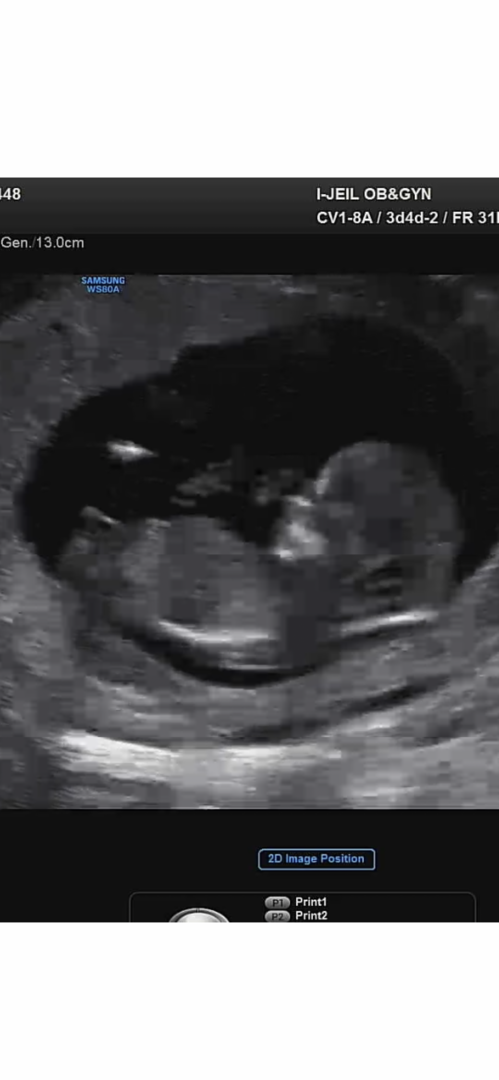

재미로 보는 각도법-!고견부탁드립니다!

ㅇ ㅏ 사진마다 좀 애매해요~~객관적으로 보기가 너무 어려워요>.<ㅋㅋㅋ

아들같아용

아들같아요